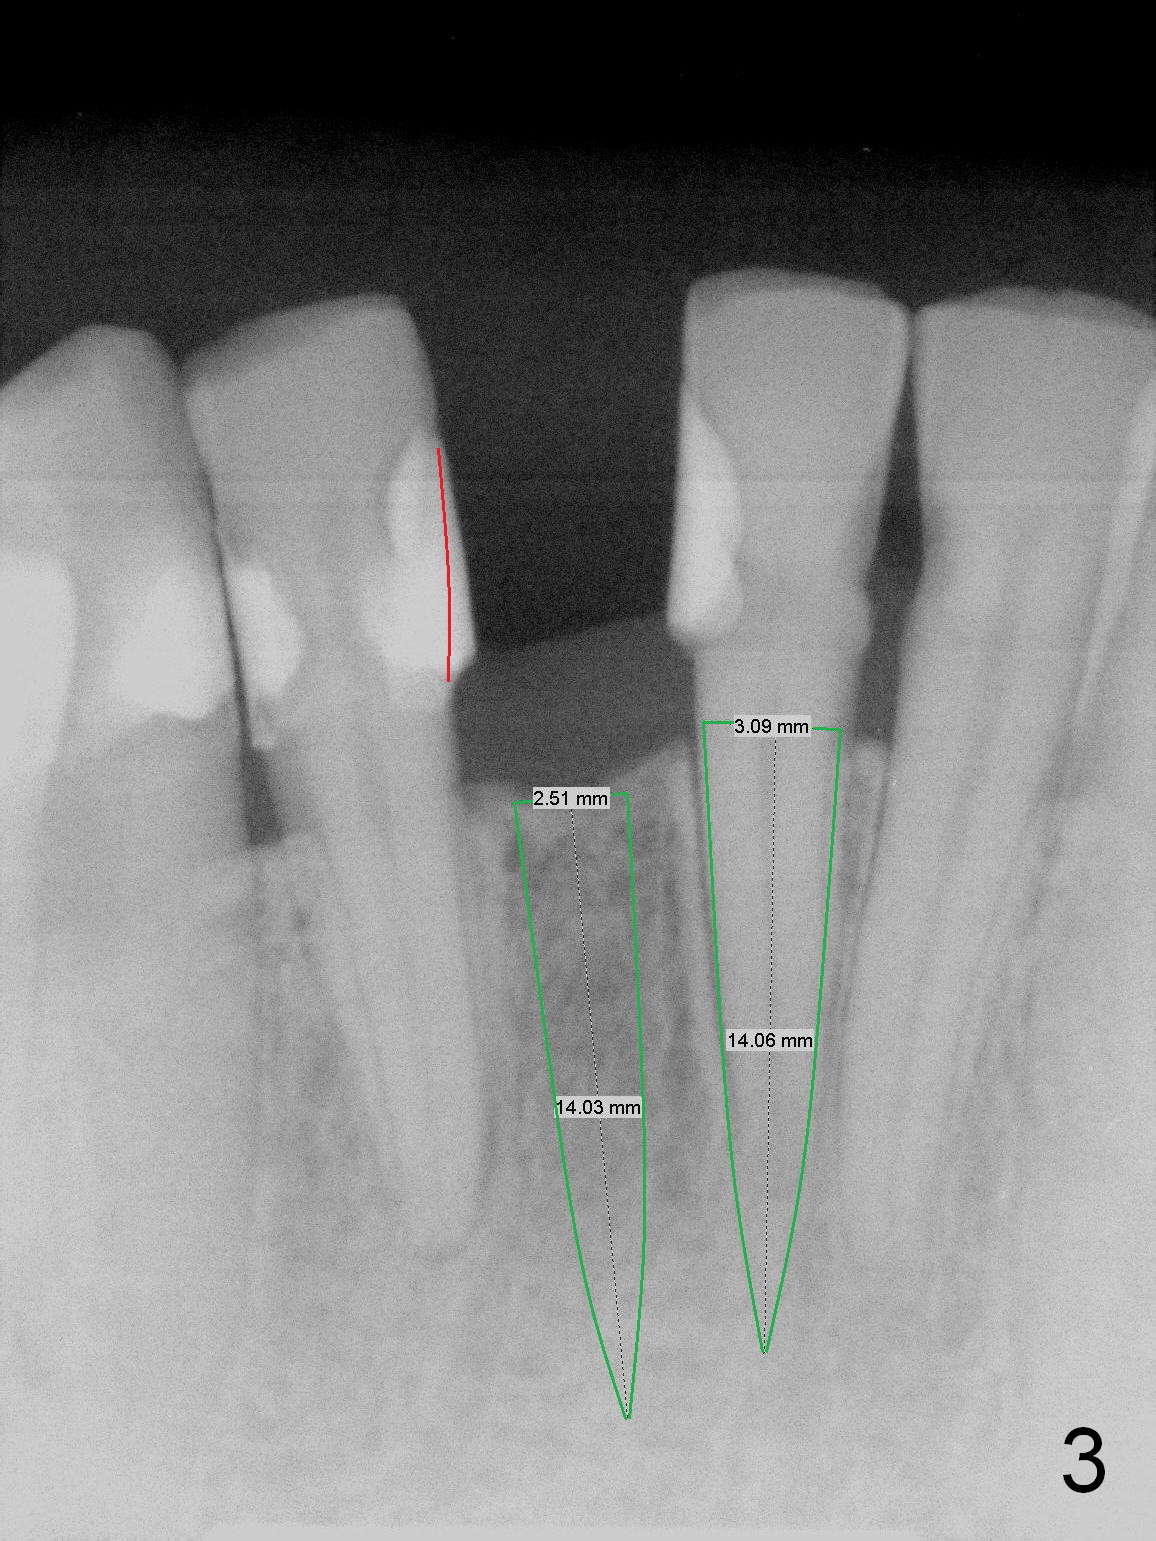

A 3 or 3.5 mm 1-piece implant is placed at #24 (Fig.3) after Metronidazole socket soaking. The larger one is chosen (3.5 mm (Tatum)) if the implant at #25 fails to be placed. A dummy implant is placed partially to test trajectory. If the latter is bad, use an angled 1-piece one (Tatum). The composite overhang (Fig.2 *) is to be trimmed (Fig.3 red line). Take preop photos to show the concave buccal plate (Fig.4a) and intra- and post-op ones to show bone expansion (Fig.4b-d).